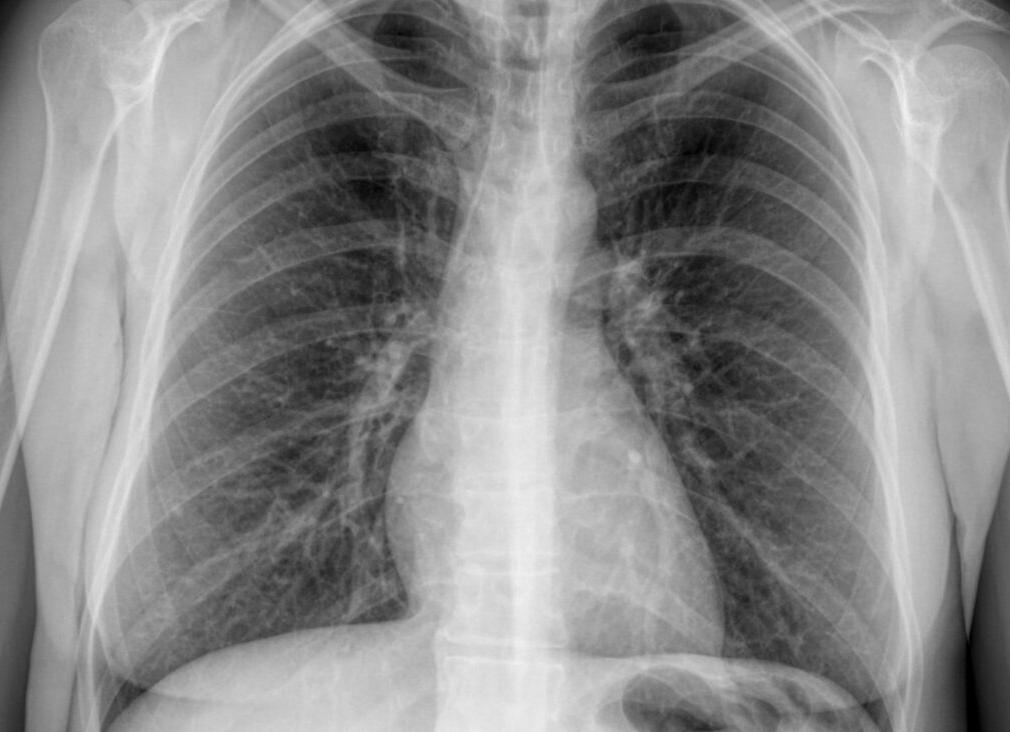

Ещё чем флюорография отличается от рентгена лёгких не в свою пользу, так это чёткостью и размером изображения на снимке. Маленькая тёмненькая картинка может не дать врачу достаточно информации об обследуемом органе – в этом случае вас всё равно пошлют на рентген, чтобы узнать больше. Также повторная диагностика понадобится, если снимок флюорографии окажется бракованным. Рентгенография же сразу предоставляет крупное чёткое детализированное изображение, удобное для просмотра и максимально информативное.

Существенной разницы в подготовке и проведении методов не наблюдается. Отличаться эти методы будут лишь принципом выполнения изображения. Чем отличается рентген, так это более крупными размерами и детальностью, за счет чего и становится возможной постановка точного диагноза.

Более точным методом является рентгенография. С ее помощью получают больше информации, что обеспечивает постановку правильного диагноза.

По рентгеновскому снимку можно установить особенности болезни, степень ее распространения и многие иные характеристики. Это повышает эффективность лечения. Кроме этого, с помощью рентгена можно наблюдать динамику процесса выздоровления. Флюорография таких возможностей не предоставляет.

В качестве дополнительного и более информативного метода назначается обязательная рентгенография легких. Она представляет собой коротковолновое электромагнитное излучение узкой направленности, которое проходит сквозь ткани организма, оставляя затемнения различного уровня исходя из пропускной способности тканей. У костей эта способность ниже, и негативная энергия рентгеновских лучей выражена ярче. Светлые участки на снимке будут называться затемнением, в противоположность цвету на изображении.

С помощью рентгена хорошо распознаются острые и хронические заболевания легочного аппарата, новообразования. Болезнь легко определить на ранних стадиях развития и отличить разные патологии по характерному рисунку. Если пациента с жалобами беспокоит кашель, одышка, боль в груди, хрипы, то не возникает необходимости направлять его на флюорографию. Ему будет назначено направление на рентген- исследование. Полученная доза радиоактивного облучения от процедуры будет равна двухнедельной, которую человек получает в обычной жизни. С помощью рентгеновских лучей можно диагностировать весь человеческий организм. Изображение получается очень точным и четко видны структурные особенности исследуемых тканей.